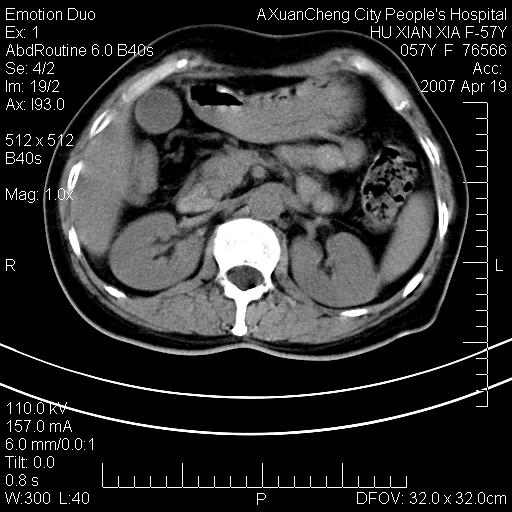

标题: CT7778:[原创]F,57Y腹痛待查,胸片提示肺部占位,应当很典型 [打印本页]

标题: CT7778:[原创]F,57Y腹痛待查,胸片提示肺部占位,应当很典型

胸片提示肺部占位

考虑:1、双侧肾上腺占位.2、肝左叶内侧段不规则低密度灶,建议强化扫描.

忽略了,只以为急腹症,应该支持肺癌肾上腺转移,肺癌患者20-30%发生肾上腺转移

双侧肾上腺增大,有分叶,密度均匀,考虑转移建议查原发灶

1.双侧肾上腺占位,转移首先考虑。

2.肝硬化,门静脉高压;肝左叶内侧段病灶建议增强。

双侧肾上腺结节样肿块,结合肺部肿块,考虑肺癌肾上腺转移。

双侧肾上腺及腹膜后淋巴结增大,结合胸片提示肺部占位,考虑肺癌双侧肾上腺及腹膜后淋巴结转移.